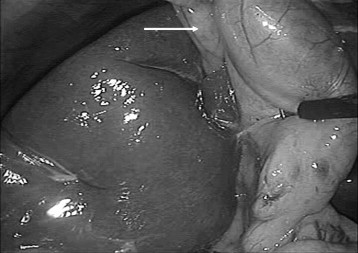

A 50-year-old woman with no medical history was admitted to our department with a history of 2 years' intermittent pain in her right upper abdomen, radiating to the back. There was no history of jaundice. The physical examination showed tenderness in the right upper quadrant of the abdomen without a Murphys sign. Laboratory findings demontrated normal rates of total bilirubin, alkaline phosphatase, γ-glutamyl transpeptidase, and C-reactive protein. Abdominal ultrasonography showed gallbladder stones without dilatation of the bile ducts. The patient underwent a laparoscopic cholecystectomy using the French position and four ports positioned as usual. The gallbladder was absent from its normal location. Medial exploration of the falciform ligament under the left liver revealed the gallbladder attached to a shallow fossa in the liver (Fig. 1). The cystic duct joined the common hepatic duct on the right side after making a hairpin bend, and the cystic artery originated from the right hepatic artery. Retrograde cholecystectomy was undertaken using electrocautery followed by intraoperative cholangiogram which showed neither dilatation of the bile ducts nor associated congenital anomalies of the biliary tree (Fig. 2). The patient was discharged on the first postoperative day, and had an uneventful postoperative period. Histological examination showed chronic cholecystitis.

After cholecystectomy, the photo shows the gallbladder bed (White arrow) to ...

Figure 2.

After cholecystectomy, the photo shows the gallbladder bed (White arrow) to gauci of falciform ligament. Inset: The intraoperative cholangiography shows a biliary modal mapping.